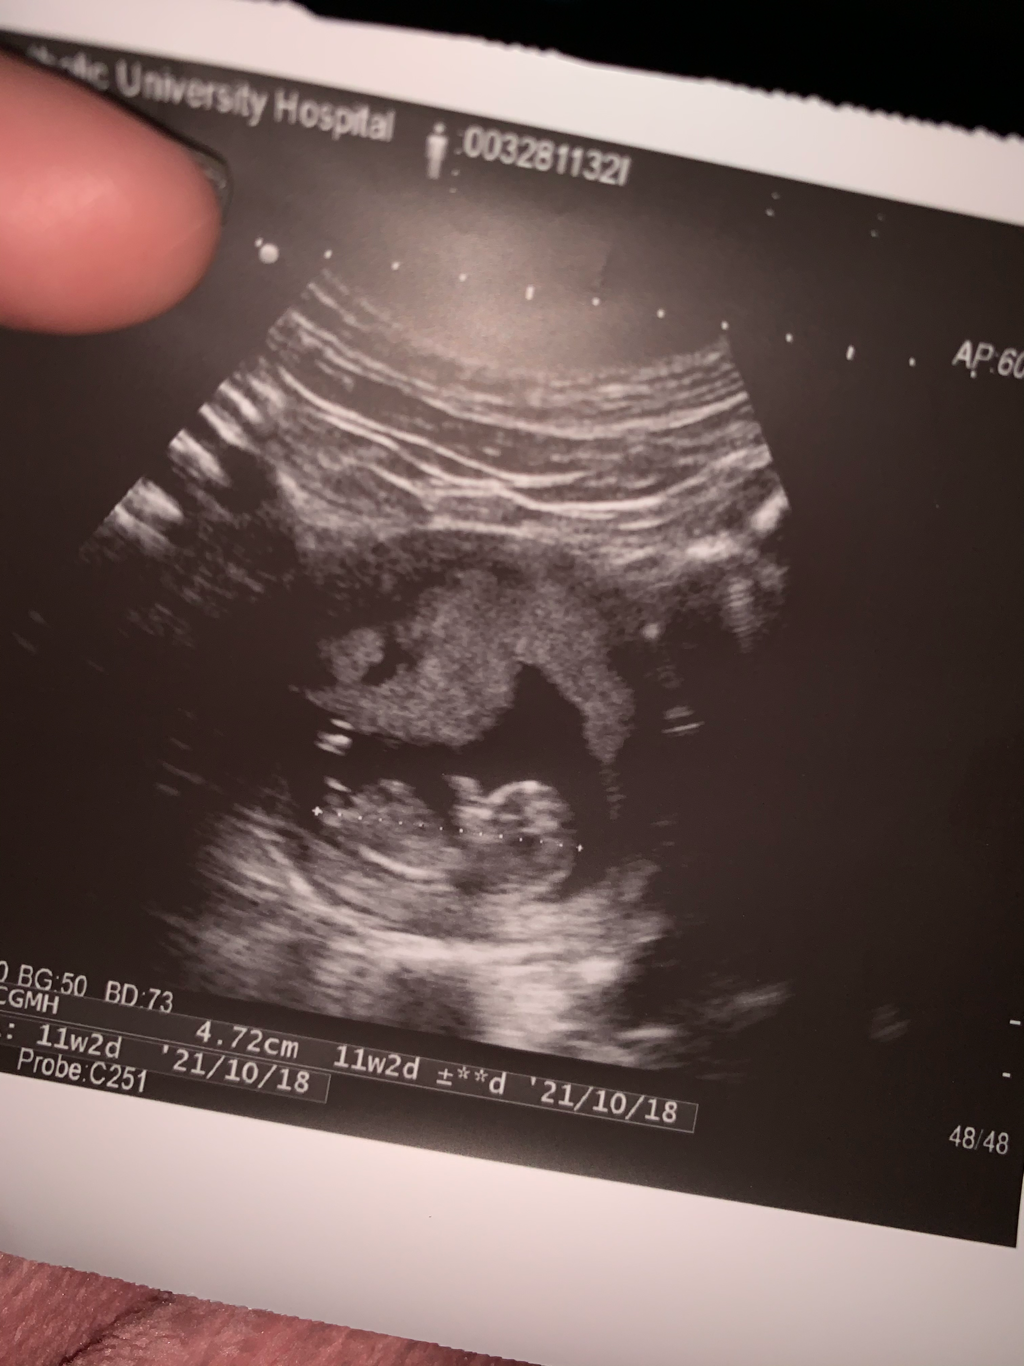

照超音波11週3天

今天去婦產科照超音波,因為這是我的第一胎,沒有經驗,很想知道圖中的寶寶的性別,有媽咪看得出來是女生還男生嗎?